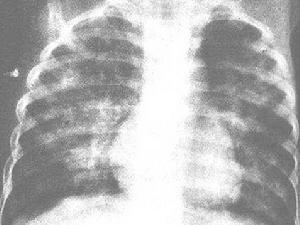

X線胸片可見雲絮狀斑片影,大小、形狀及位置都不恆定,呈遊走樣,於短期內消失及另一部位再發。偶見雙肺瀰漫顆粒狀陰影需與粟粒性肺結核鑑別。

近年來有一種"嗜酸細胞增多性哮喘病"或"暴發性哮喘性嗜酸細胞增多綜合徵",在國內若干地區暴發流行,可見於嬰幼兒、年長兒至成人。患兒不發熱或有低熱,突出表現為哮喘與乾咳,有時出現瘙癢性皮疹。病情嚴重時,偶可因支氣管、毛細支氣管梗阻及心力衰竭而危及生命。X線胸片上多數有肺紋理增加及肺氣腫,少數有片狀或網點狀陰影(圖2410)。血內嗜酸細胞增多可高達20%以上。病因未明,有些作者認為是蛔蚴在體內移行的表現,有人推測一部分流行可能與病毒感染或真菌孢子大量吸入有關。